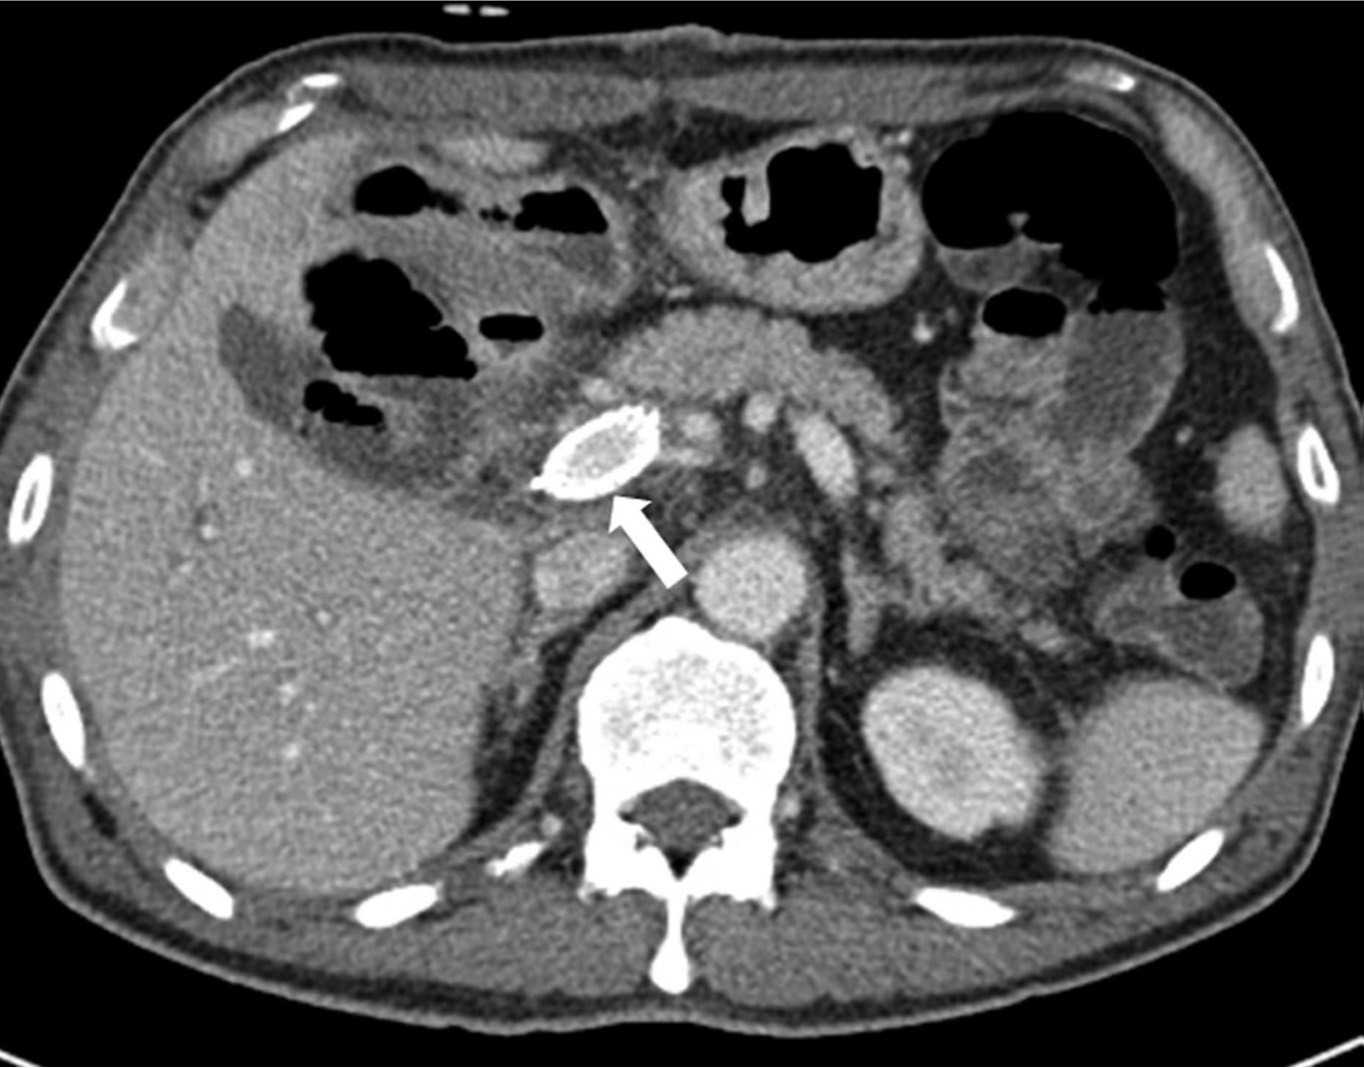

Figure 3. Contrast-enhanced CT study taken 5 days after the portal vein stent insertion. Stent is located in the main portal vein (arrows in A and D), with patent portal flow (B and C).

초음파 유도하에 간우엽 S6 담관을 천자하여 5Fr sheath(Terumo, Tokyo, Japan)를 삽입하고 5Fr KMP catheter(Cook, Bloomington, IN, USA)를 상장간막정맥에 위치시키고 시행한 직접 문맥조영술에서 주문맥에 부분적으로 폐쇄가 관찰되었고(Fig. 2a) 혈전으로 인한 폐쇄로 생각이 되었다. 7F McNamara sheath(Cook, Bloomington, IN, USA)를 삽입하여 흡인 혈전제거술을 수차례 시행하여 소량의 혈전이 흡인되었으나 문맥 혈류는 여전히 막혀있었음. 이에 12mm balloon(EverCross, EV3, Plymouth, MN, USA)으로 경피혈관확장술을 시행하였으나 이후 시행한 문맥조영술에서도 문맥 폐쇄 소견은 여전히 보였음. 이어 주문맥에 14x40mm 자가팽창형금속 스텐트(ELuminexx, Bard, Tempe, AZ, USA)를 설치하였으나 문맥에 폐쇄된 분절을 전부 포함할 수 없어 근위부에 12x4cm의 자가팽창형금속 스텐트(Zilver, Cook, Bloomington, IN, USA)를 추가로 설치하고 이후 12mm balloon으로 혈관확장술을 시행하였음. 마지막으로 시행한 문맥조영술에서 문맥은 개통되어 혈류는 회복되었으나 문맥 원위부에는 혈전이 일부 남아있었음(Fig. 2b). 천자한 통로는 histoacryl로 색전후 시술을 종료하였음. 간문맥 스텐트 설치 후 5일 뒤 시행한 CT에서 문맥 스텐트는 개통되어 있었고 조영 후 사진에서 문맥 혈류가 말초까지 가는 것을 확인할 수 있었음(Fig. 3). 환자는 이후 간기능 부전 및 문맥 고혈압의 증상 및 소견 없이 회복하여 퇴원하여 외래 추적 관찰 중임.